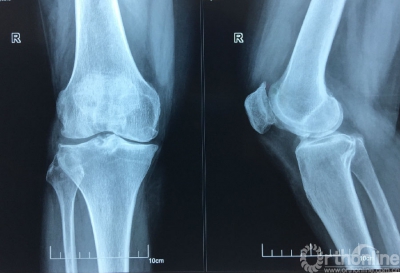

5月27日上午,山西医科大学第二医院骨科关节组副主任医师张民及其手术团队借助3D打印技术,成功为一位55岁的患者实施保膝截骨手术。标志着山西省首台3D打印保膝截骨手术取得成功,此项新技术的开展,为广大骨关节病患者带来了福音,此类疾病患者中逾1/3可终身保有自身关节,不再需要置换人工关节。

患者杨某患双膝骨性关节炎6年,关节变形,疼痛难忍,近几个月病情加重,5月22日到山医大二院骨科就诊。当得知该院可使用3D打印个性化定制截骨导引板进行胫骨平台高位截骨手术,手术时间只需要20多分钟,且费用是置换人工关节的一半。这一技术保留了患者自身的膝关节,术后能完全恢复自身膝关节的生理功能,而且以后还可以继续做农活时,决定接受3D打印截骨手术。

膝关节骨性关节炎是一种以退行性病理改变为基础的中老年人常见病。对于畸形较轻、较年轻的患者,首选保膝治疗。保膝治疗是一种既可纠正畸形,减轻疼痛,又可保留患者自然的膝关节,最大程度的保留关节的运动功能和舒适性的一种治疗方案,可以延缓关节置换的时间,甚至终身不必置换关节。保膝治疗包括药物治疗、胫骨截骨术和单髁置换术,与全膝关节置换术构成了膝关节骨性关节炎的“阶梯性治疗”,“保膝”和“换膝”并举。根据患者病情发展的不同阶段,畸形程度,年龄和功能需求等因素,提供不同的手术选择,真正做到“精准医疗”。

“高位胫骨截骨手术(HTO)已经开展多年,但是,之前由于手术难度高,如果没有精确的角度、深度、斜率等数据为依据,很可能对患者造成骨折及多项病发症,一般都需要具有丰富经验的临床医生才敢实施手术。”通过相关精密设备采集患者数据,并分析制定出个性化手术方案,打印出手术中导引手术角度、深度等6个精准化数据的导板,手术时间缩短了一半以上,且术后患者不仅膝关节疼痛即刻缓解,2-3天左右就可在适当的护膝辅具下,轻踩试走。高位胫骨截骨手术(HTO)最大限度保留患者机体功能,对于术后生活质量要求高及活动度大的患者,成为很好的选择。